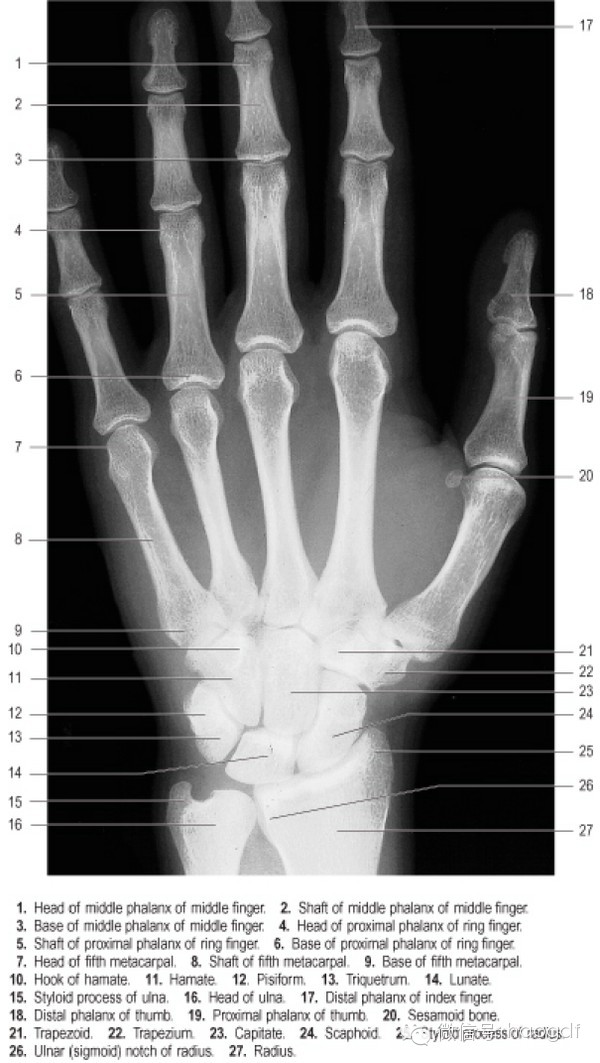

这个问题实际上并不是所谓女性化动作这么简单。可以从神经控制(体感皮层、手指神经支配)和肌肉控制两方面解释。

在体感皮层,不同的区域控制不同的躯 / 肢体。而且各躯 / 肢体在体感皮层中对应的区域大小,跟躯 /

肢体的大小不是比例关系,而是跟体感控制的复杂度有关。如果把体感皮层中不同区域反向映射到躯 /

肢体,并对应上皮层中的体积大小,就得到了所谓体感小人(Somatosensory homunculus):

可以看到,控制手掌 /

指、舌头的脑区很大,而控制脚、腿、胳膊的区域这相对较小。前一组在人体上的大小虽然比较小,但是其控制复杂程度要远远大于后一组躯 /

肢体器官。具体到手指的控制,大拇指、食指、中指、无名指和小指的体感区域大小递减 ![[1] [1]]()